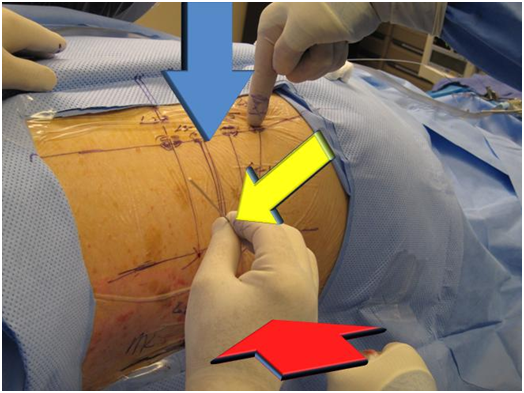

Intra operative determination of portal of entry by GPS1

C-arm fluoroscopy is used to identify the lumbar levels requiring surgery. The midline of the spine (by connecting the lumbar spinal processes under fluoroscopy) and foraminal line of the spine (by connecting the neuro-foramen under fluoroscopy) are first identified by using a flexible stylette under fluoroscopy. A transverse disc space-line (representing the horizontal disc plane), is drawn under fluoroscopy, starting at the foramen line by using a flexible stylette and intersecting with the midline of the spine. The portal of entry for lumbar spinal surgery is marked on the transverse disc space-line with a marking pen. The distance of the point of the portal of entry from the midline varies with the height and weight of the patient. In an average-sized patient it is approximately 12 cm at the affected disc level. The more obese the patient, the greater the distance of the portal of entry point is from the midline in order to accommodate for excess subcutaneous fat.

Following GPS localization, local anesthetic is injected along the surgical trajectory the Kambin safety triangle to treat disc herniations (Figure 3–6, Figure 8, Figure 9). A long stylette is introduced through the identified entry point (as explained above) (Figure 10). The stylette is directed towards the disc through the Kambin Triangle (Safety zone) (Figure 3). The Kambin triangle is the site of surgical access for posterolateral endoscopic lumbar discectomy. It is defined as a right angled triangle over the dorsolateral disc. The hypotenuse is the exiting nerve, the base (width) is the superior border of the caudal vertebra, and the height is the traversing nerve root and dura.

Figure 5 (a) Identifying the foraminal line on patient (b) Fluoroscopic lateral view (c) Fluoroscopic midline or lateral foraminal line (On AP View).

Figure 6 (a, b) Flexible stylette is used to identify the intersection of the L4/5 disc space line with the foraminal line, on patient and under fluoroscopy.

Figure 7 (a, b) L5/S1 disc can be accessed through the same skin puncture entry through a steeper angle, on patient and under fluoroscopy.

Figure 8 Completed GPS (grid positional system).

Note: L4/5 disc portal of entry point can be used to access both L4/5 and L5/S1 discs by applying different angles to the trajectory of the stylette, perpendicular (for L4/5 disc) vs. steeper angle (for L5/S1 disc).

Figure 10 Stylette is introduced at an angle of approximately 45 degrees accurately toward the foramen in the GPS grid, under fluoroscopy.